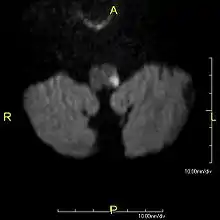

Examens complémentaires

La lésion sera le mieux vue sur une IRM cérébrale.